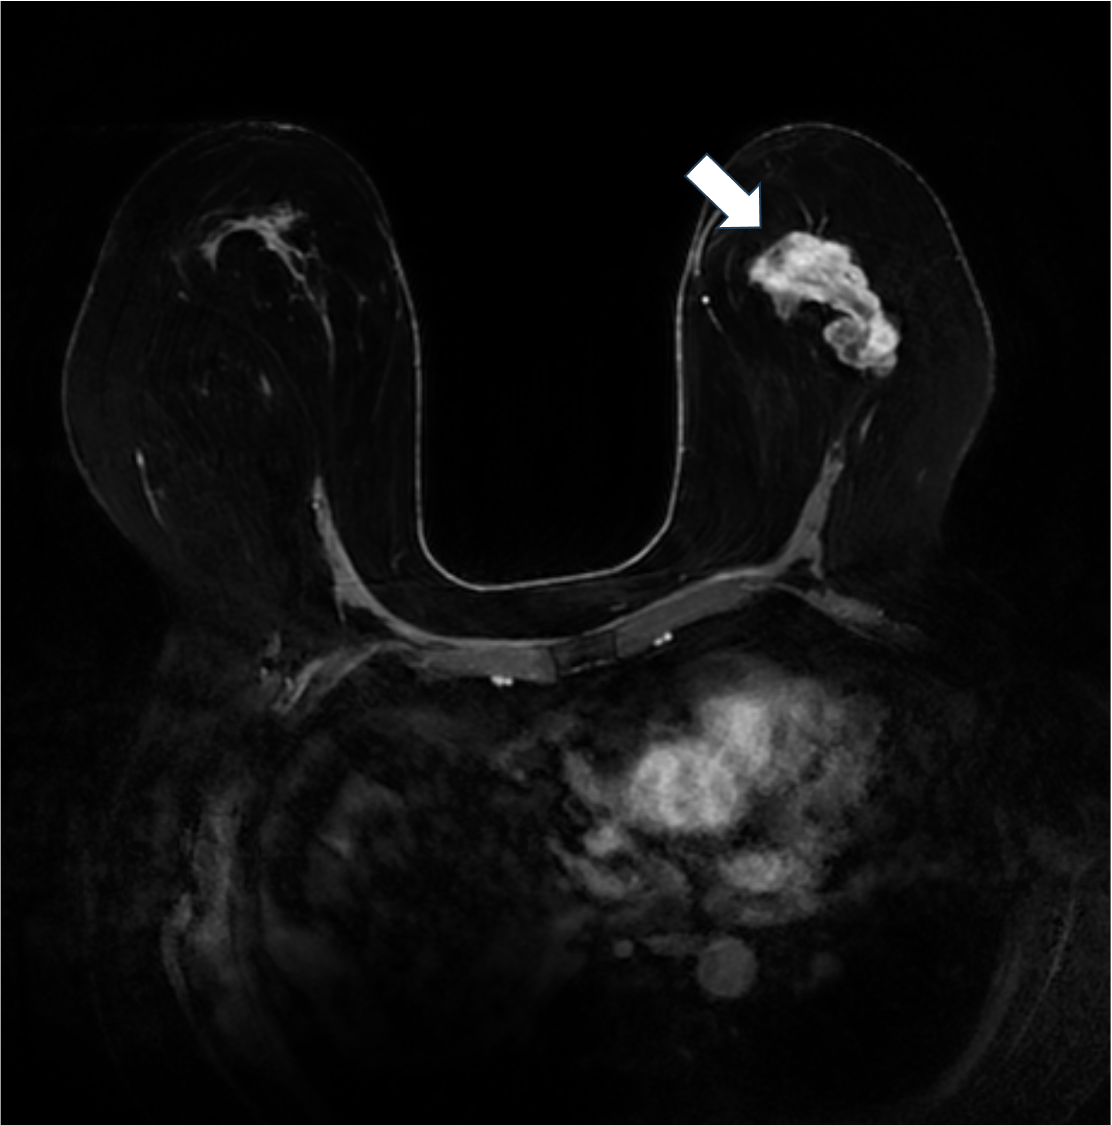

6. ダイナミックMRI 早期相 MIP像

左乳房に不整形腫瘤を認める。MIP像は一目で病変全体を把握することができる。MIP像でも乳頭側の造影効果が強いことが分かる。